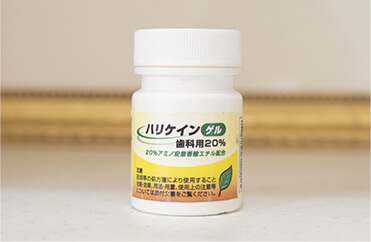

麻酔時に歯ぐきの表面に塗布することによって、針が刺さる際の痛みを感じにくくすることができます。